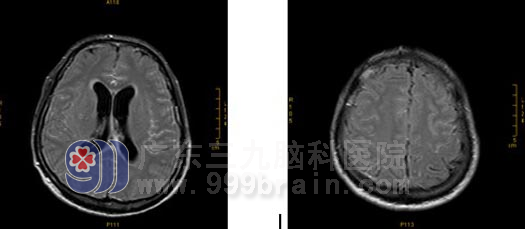

影像学表现

平扫: 双侧基底节区及双侧大脑半球皮层下白质内多发病灶,幕上轻度梗阻性脑积水。

增强扫描:基底池、桥前池及双侧外侧裂池软脑膜均可见明显强化;桥脑、小脑及双侧大脑半球可见散在的斑点状异常强化灶